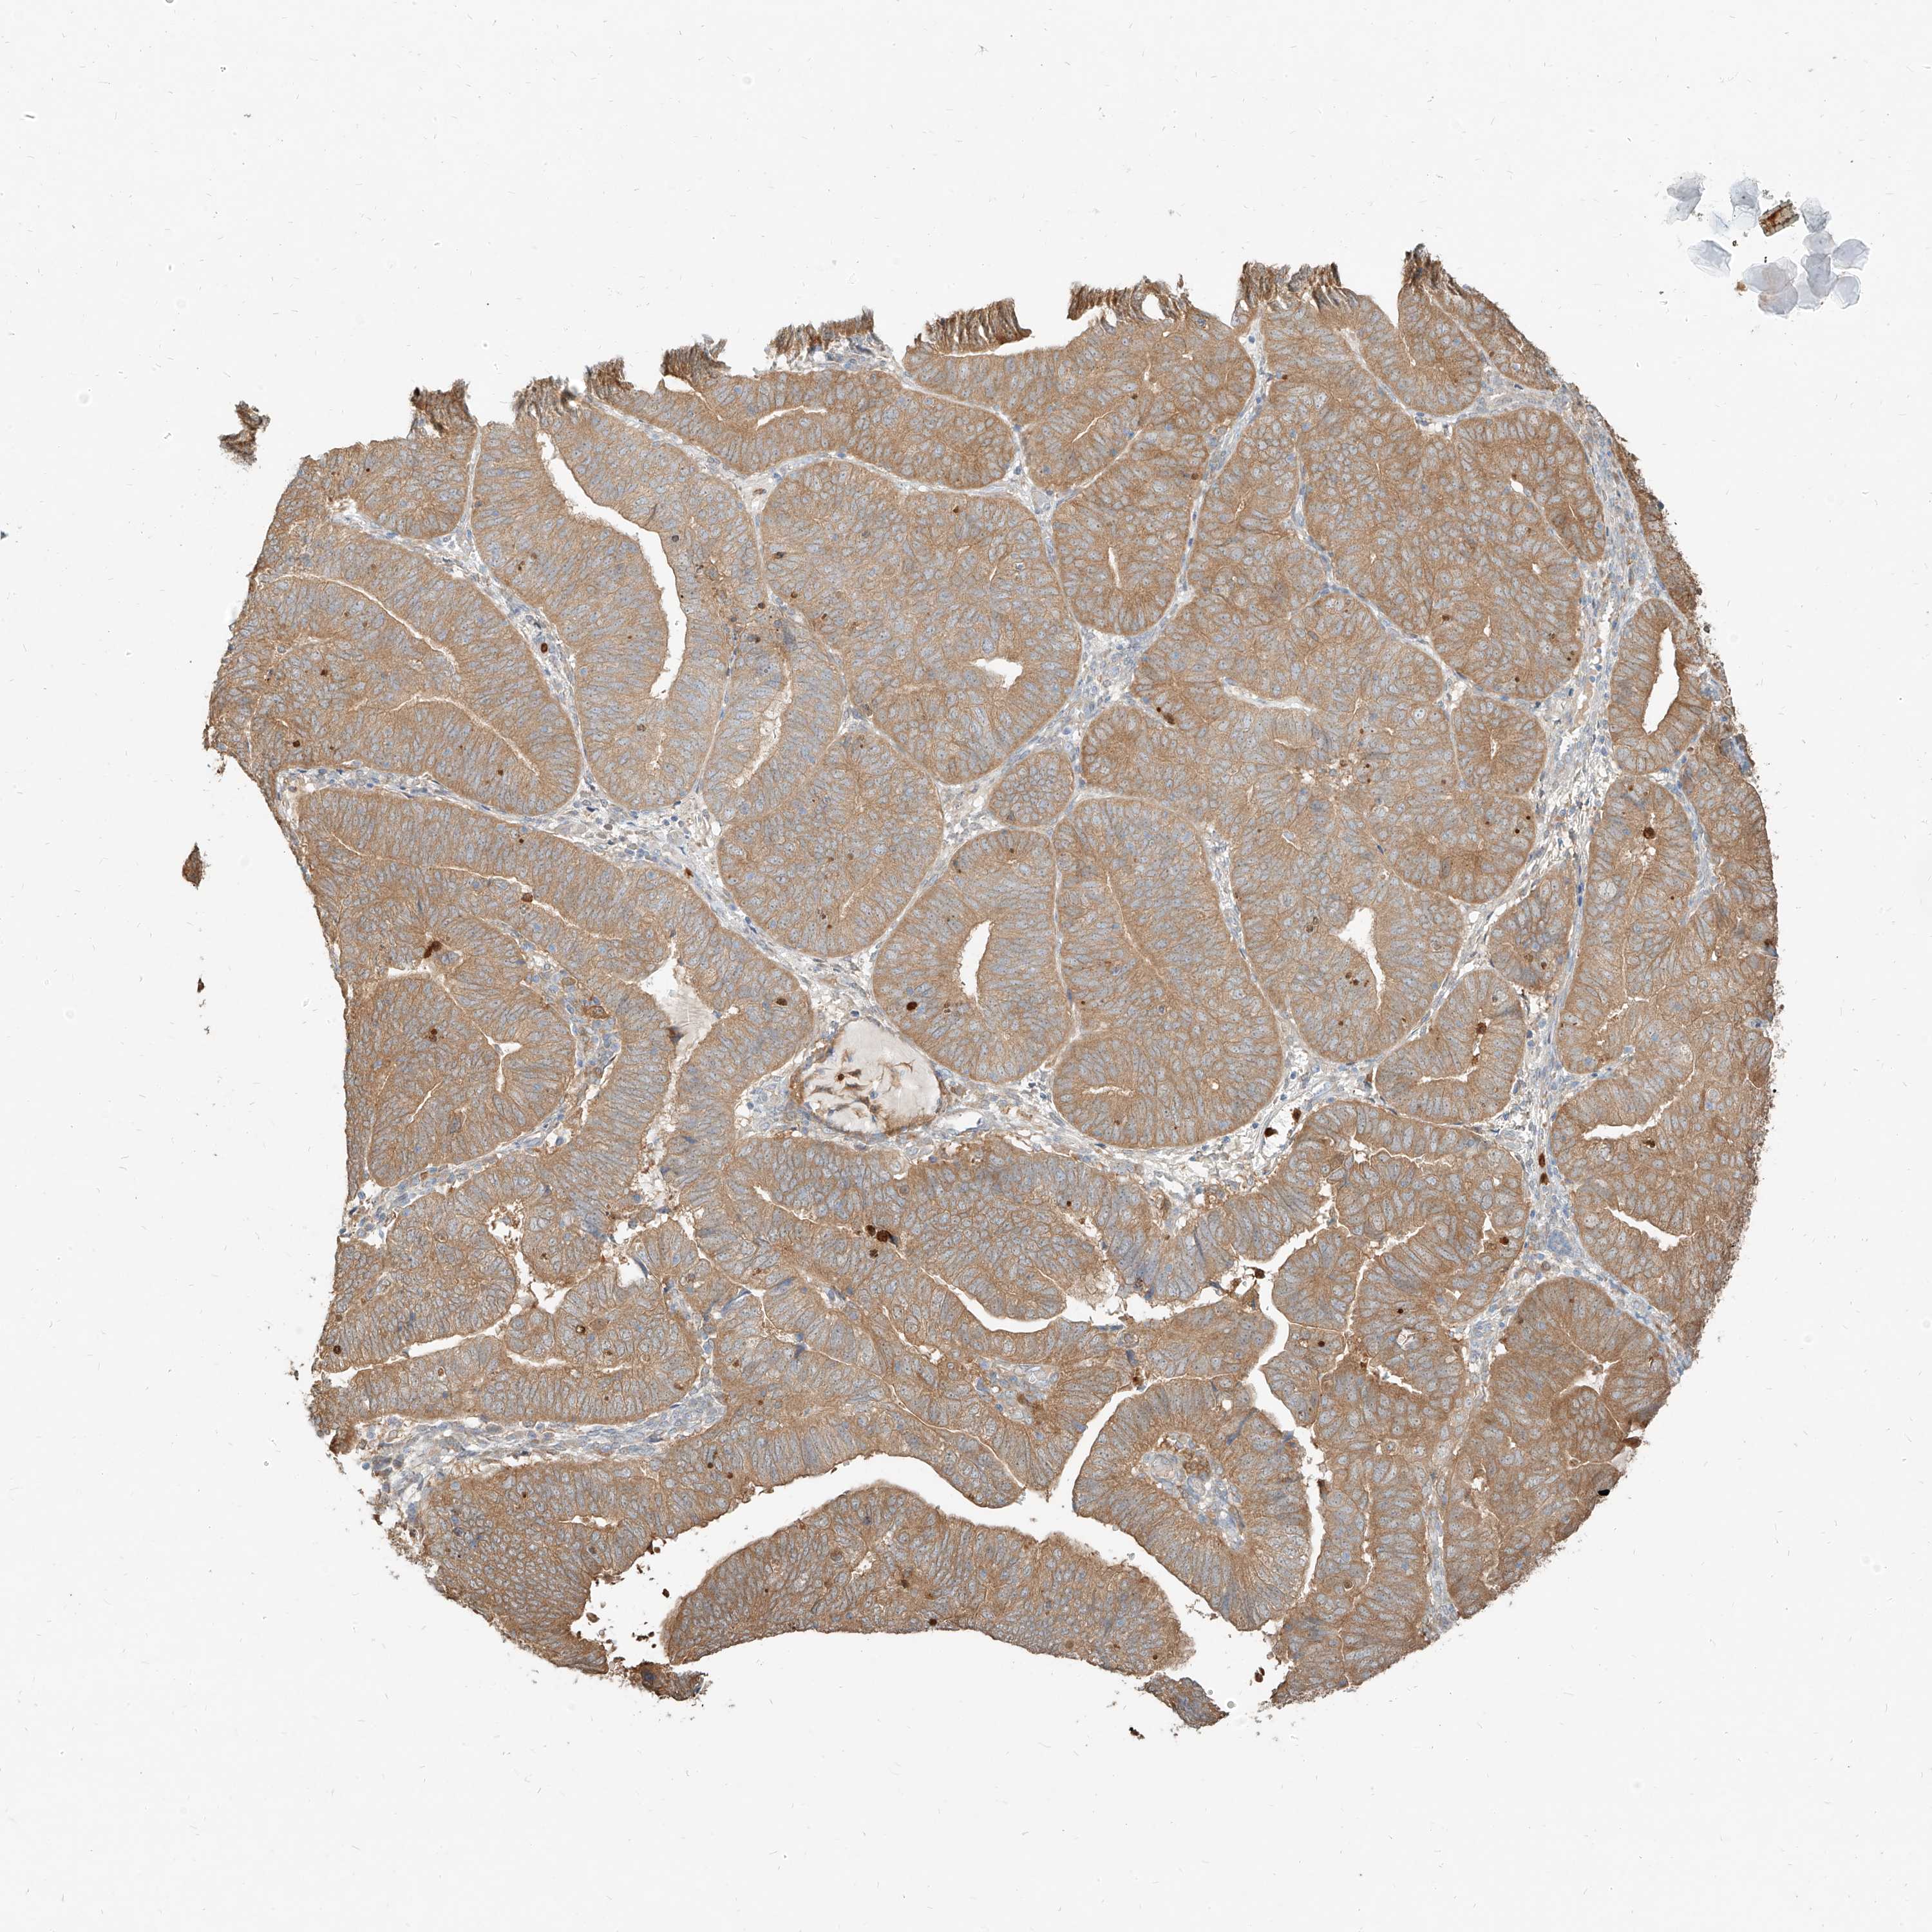

ENDOMETRIAL CANCER - Protein expressioni

A mouse-over function shows sample information and annotation data. Click on an image to view it in a full screen mode. Samples can be filtered based on level of antibody staining by selecting one or several of the following categories: high, medium, low and not detected. The assay and annotation is described here.

Note that samples used for immunohistochemistry by the Human Protein Atlas do not correspond to samples in the TCGA dataset.

Antibody stainingi

Antibody staining in the annotated cell types in the current human tissue is reported as not detected, low, medium, or high, based on conventional immunohistochemistry profiling in selected tissues. This score is based on the combination of the staining intensity and fraction of stained cells.

Each image is clickable and will lead to virtual microscopy that enables deeper exploration of all samples and also displays staining intensity scores, fraction scores and subcellular localization as well as patient and tissue information for each sample.

Antibody HPA031314

Antibody HPA031315

Staining

High

Medium

Low

Not detected

Intensity

Strong

Moderate

Weak

Negative

Quantity

>75%

75%-25%

<25%

None

Location

Nuclear

Cytoplasmic/membranous

Cytoplasmic/membranous,nuclear

Adenocarcinoma, NOS